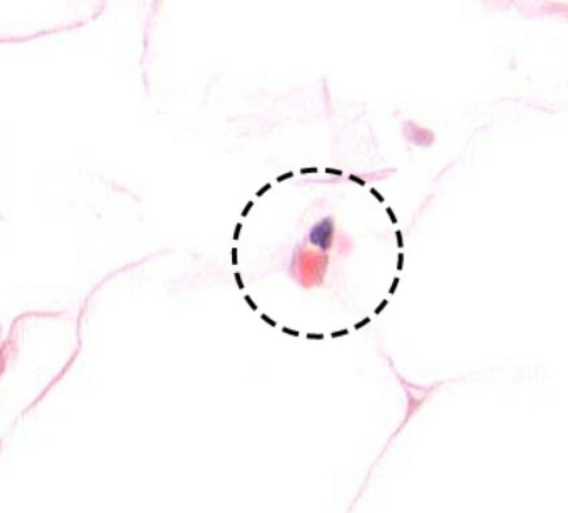

Capillaries/ Postcapillary v. |

單層 |

無 |

pericyte |